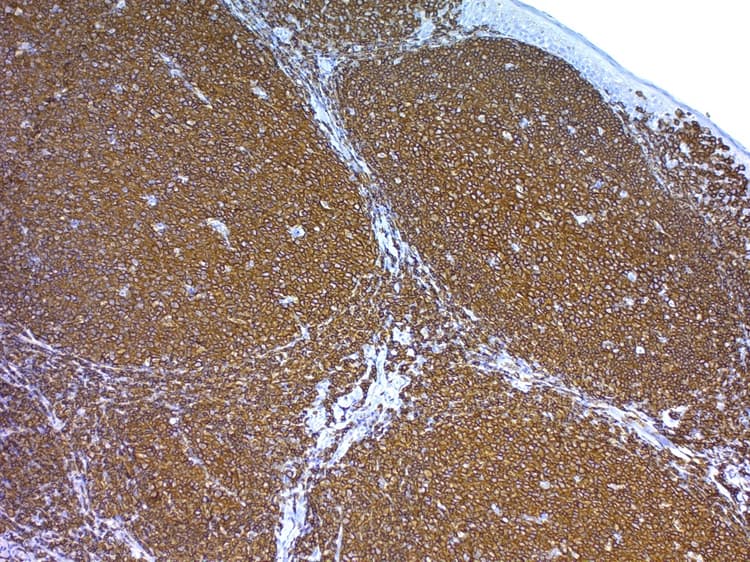

Antigen Retrieval Buffer (100X Tris Buffer, pH 10.0) is a special solution that enables rehydrate and target retrieval in formalin-fixed, paraffin-embedded tissue sections in one step.

Species Reactivity IHC-P